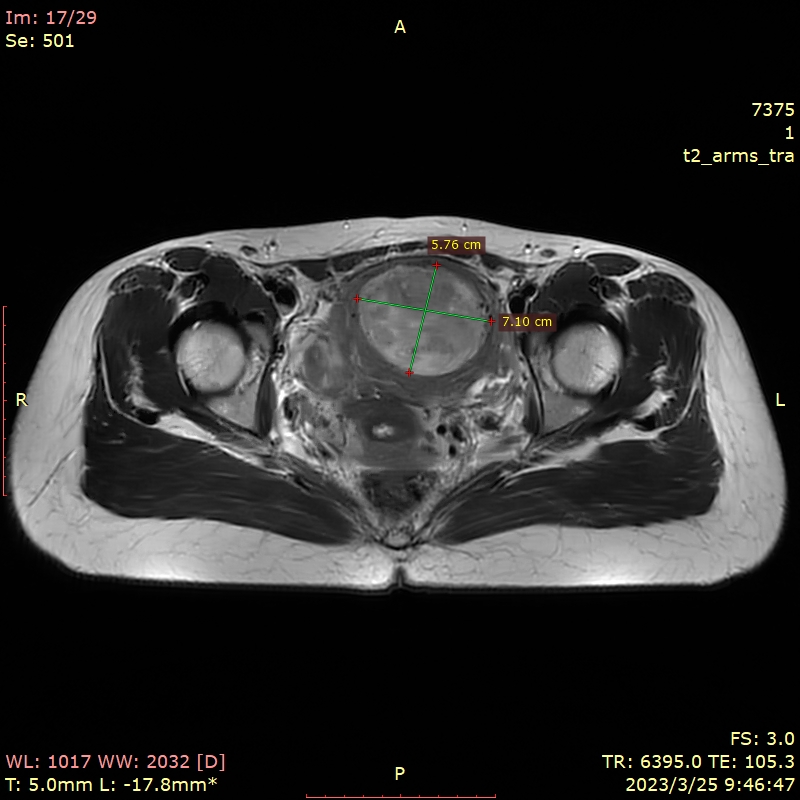

✦超声和MRI提示子宫多发肌瘤,较大者4-5型,T2高信号,71mm*58mm*67mm,次之2型,大小51mm*36mm*55mm,体检提示子宫如孕10周大小。

✦术前肌瘤大小:前壁4-5型肌瘤59mm*52mm,2型肌瘤43mm*40mm。